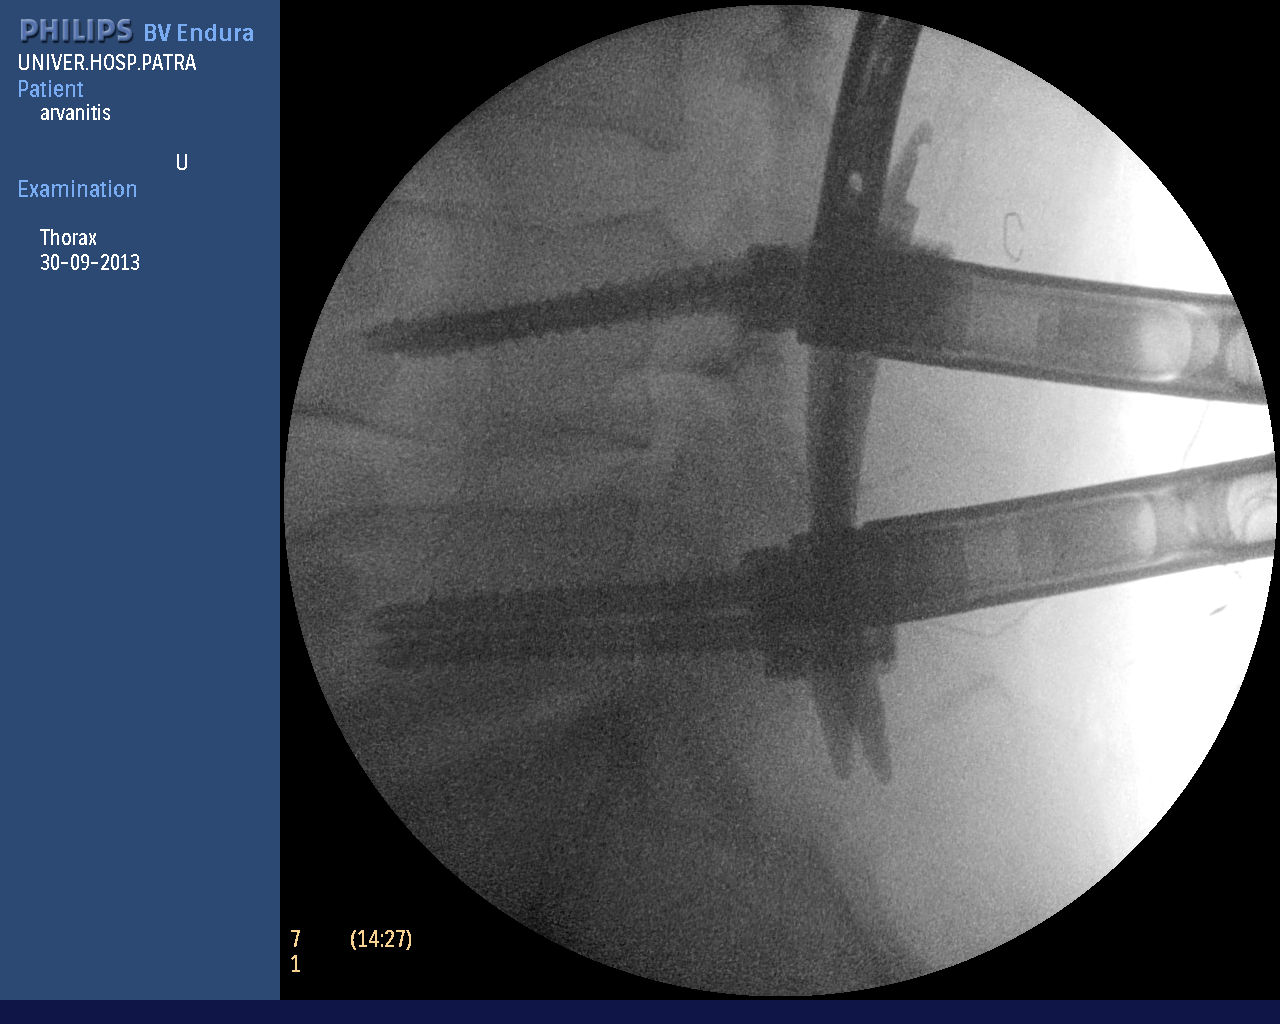

In more complex spinal problems (vertebral fractures, spondylolisthesis, instability, etc.), spinal fusion is needed, i.e. the placement of special screws and rods to stabilize the vertebrae. The operation is also performed percutaneously, avoiding tissue injury and postoperative pain. As shown in the photos (personal file) wire guides are placed and with the help of neuroplasty the screws are implanted if necessary. In every phase of the surgery the neurosurgeon sees the anatomical structures on the monitor accurately and avoids any tissue injuries.

The photographs illustrate the transdermal placement of the materials using the neuropilot which allows on-line observation of the surgeon's movements with millimetre precision.

Intraoperative radiography of percutaneous spinal fusion.